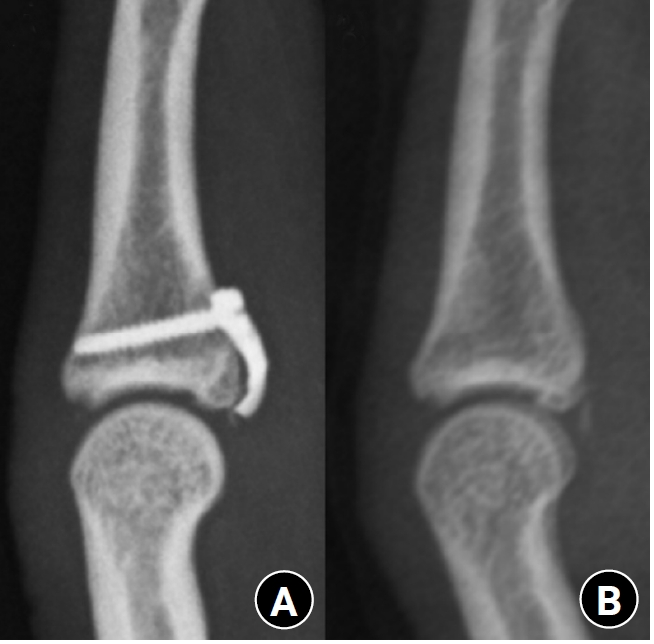

Fig. 4.

Radiographs during follow-up. (A) Bone union after treatment with the hook plate. (B) Appearance after implant removal.

Fig. 4. Radiographs during follow-up. (A) Bone union after treatment with the hook plate. (B) Appearance after implant removal.